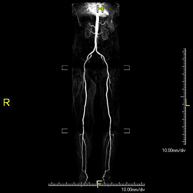

Prueba diagnóstica no invasiva que consiste en el estudio vascular del sector aorto-ilíaco y de los vasos arteriales de ambas extremidades inferiores, obteniendo imágenes de alta definición anatómica mediante el empleo de un campo electromagnético y ondas de radio (con un emisor y un receptor). Es indispensable el uso de contraste paramagnético (Gadolinio). Sin embargo, no utiliza radiación ionizante. La calidad de las imágenes permite realizar reconstrucciones en 2D y 3D. Está especialmente indicado en aquellos pacientes en los que hay sospecha de enfermedad vascular de ambas extremidades, en pacientes con enfermedad vascular de ambas extremidades como el mapa vascular antes del tratamiento (percutáneo o quirúrgico), como el mapa vascular pre-quirúrgico en pacientes con lesiones óseas o musculares que requieran cirugía, etc. - Angio-RM Arterias renales

Prueba diagnóstica no invasiva que consiste en el estudio de la arteria aorta abdominal, obteniendo imágenes de alta definición anatómica mediante el empleo de un campo electromagnético y ondas de radio (con un emisor y un receptor). Es indispensable el uso de contraste intravenoso paramagnético (gadolinio). Sin embargo, no utiliza radiación ionizante. La calidad de las imágenes permite realizar reconstrucciones en 2D y 3D. Está especialmente indicado en aquellos pacientes en los que hay sospecha de enfermedad vascular de ambas extremidades, en pacientes con enfermedad vascular de ambas extremidades como mapa vascular antes del tratamiento (percutáneo o quirúrgico), como mapa vascular pre-quirúrgico en pacientes con lesiones óseas o musculares que requieran cirugía… - Angio-RM Lesión partes blandas